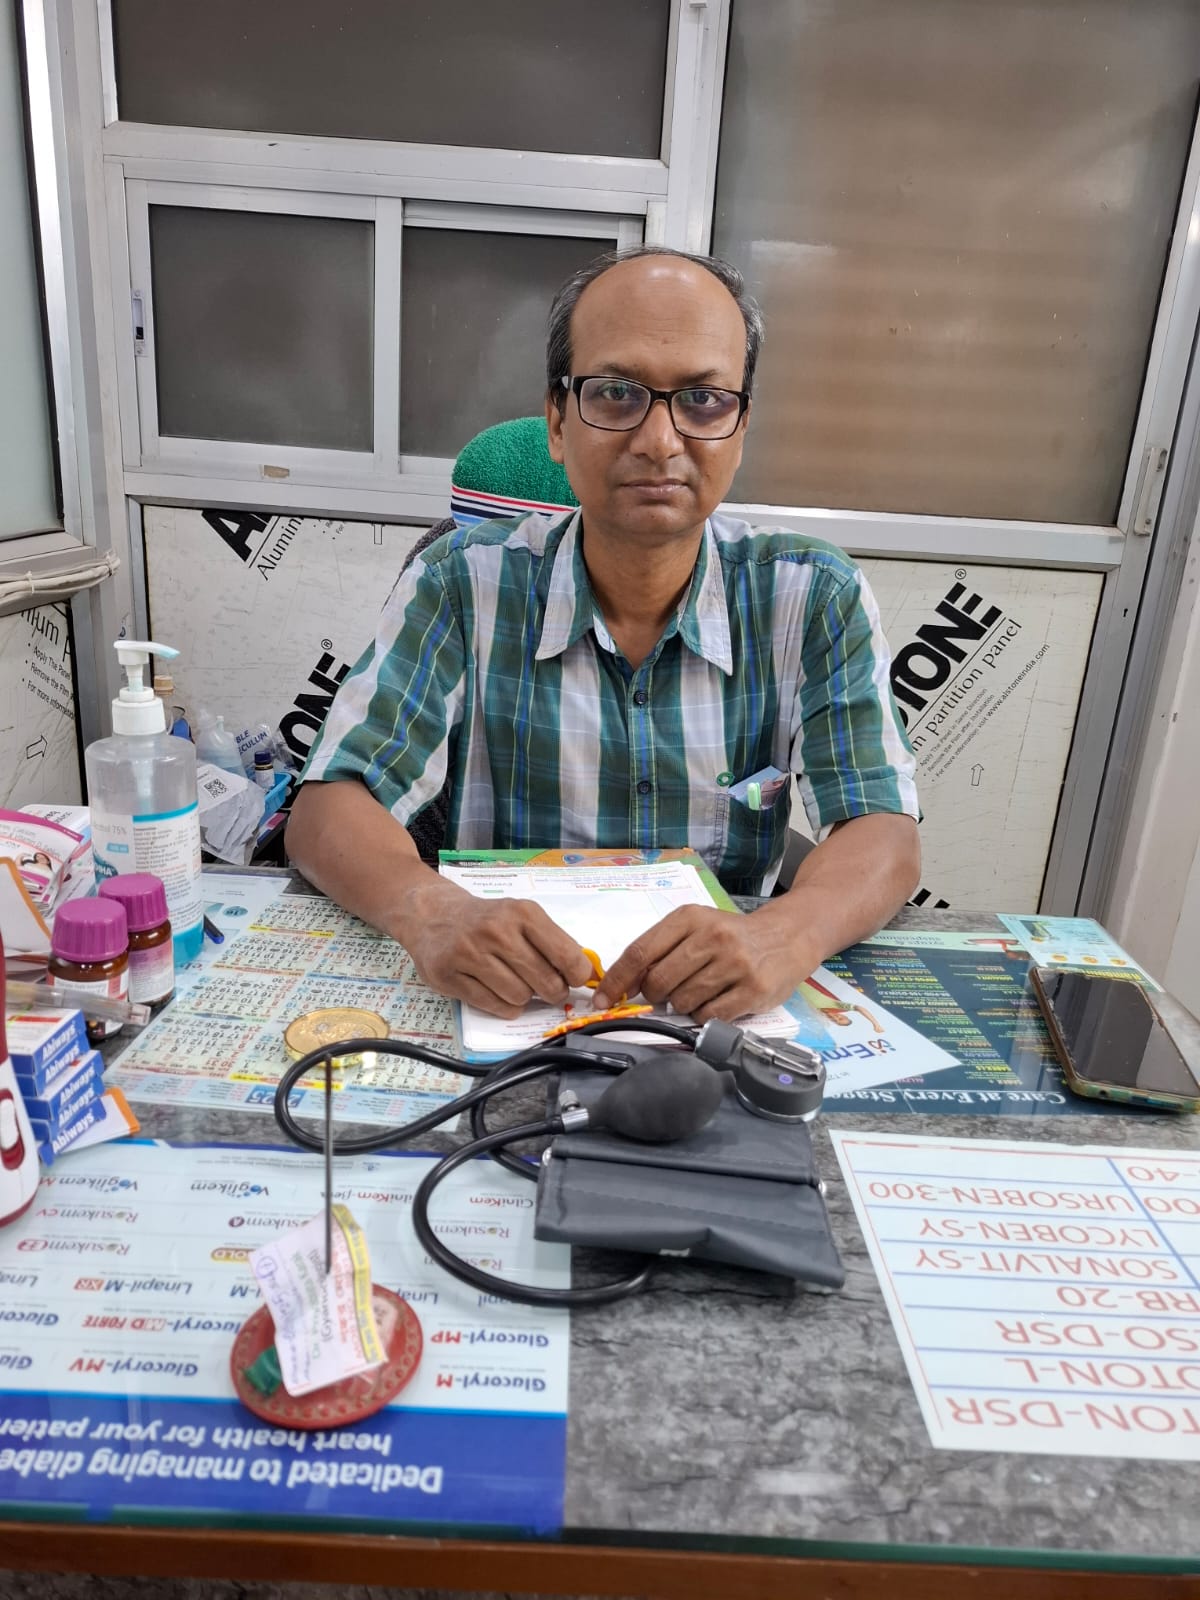

Welcome to Shankar Medical

Purulia's Most Trusted Multispecialty Clinic & Diagnostic Centre

Since 2018, Shankar Medical has been at the forefront of healthcare delivery in Purulia, West Bengal. We are committed to providing comprehensive, patient-centered medical care across multiple specialties under one roof.

Our team of highly qualified doctors and state-of-the-art diagnostic facilities ensure that you receive the best possible care. We combine medical expertise with compassion to deliver healthcare services that you can trust.